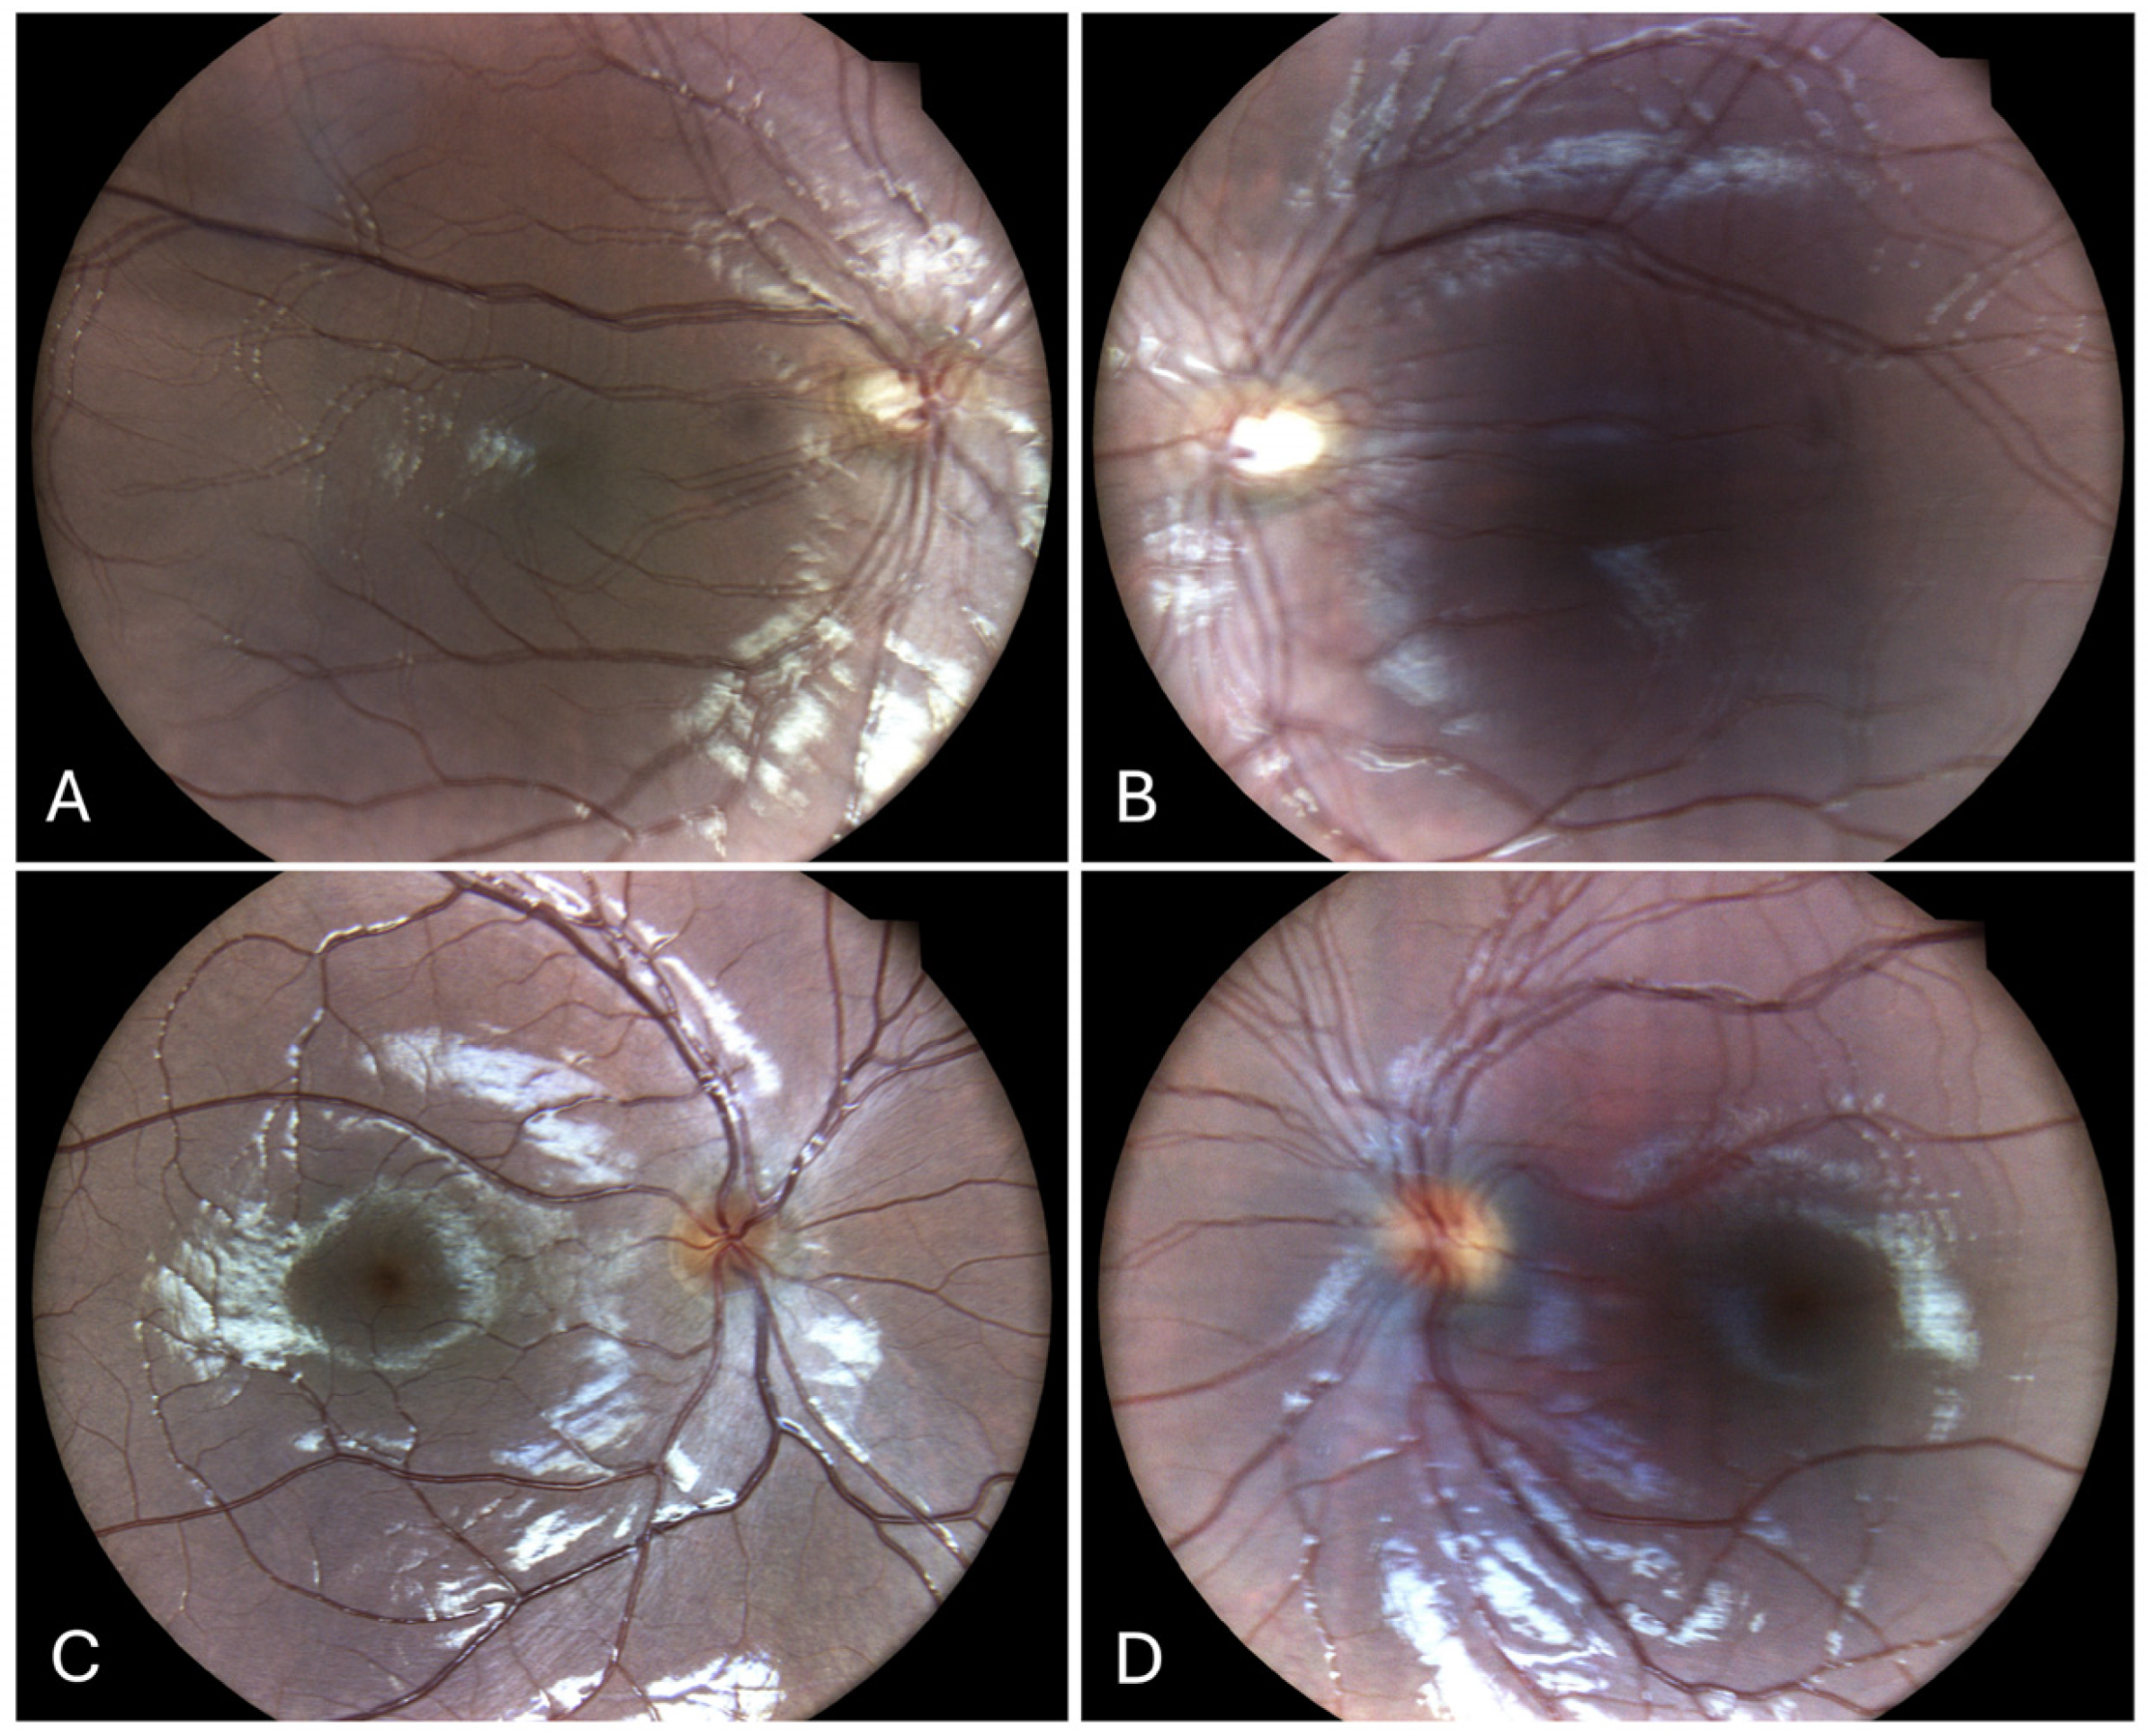

Repeated fundus photographs (Figure 3A,B) revealed double images with small-to-medium amplitude and both horizontal and vertical components in both eyes, consistent with clinical findings. The macula was normal. Blinded grading of the photographs yielded scores of 2 for the right eye and 3 for the left eye.

After surgery, he was orthoptic in primary gaze for far, with a residual 8PD for near. Fundus photography of the right eye (Figure 3C) demonstrated a normal fundus with a single image. However, the left eye image (Figure 3D) displayed a normal fundus but duplicated photos, suggesting a small amplitude horizontal nystagmus, which corresponds to the clinical finding of latent nystagmus when the fellow eye is occluded.

Figure 3. Fundus photos of Case 1 (A,B) showing double images with small-to-medium amplitude and both horizontal and vertical components in both eyes, consistent with clinical findings. The macula was normal. Blinded grading of the photographs yielded scores of 2 for the right eye and 3 for the left eye. Case 2 (C,D). 3C demonstrated a normal fundus with a single image. The left eye in image 3D displayed a normal fundus but duplicated photos, suggesting a small amplitude horizontal nystagmus, which corresponds to the clinical finding of latent nystagmus when the fellow eye is occluded.